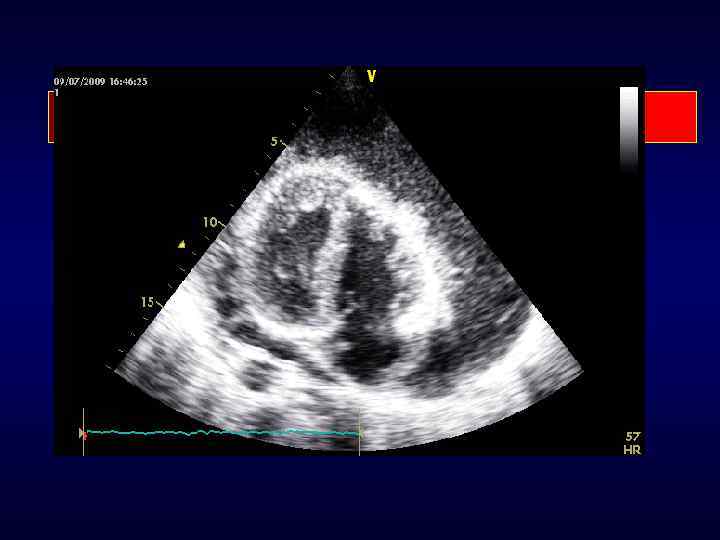

Дополнительные Эхо. КГ признаки инфекционного эндокардита: • Абсцессы • Признаки деструкции сердечных структур

АБСЦЕССЫ Анатомия Полость около клапана с некрозом и гнойным содержимым, не сообщающаяся с полостью сердца Эхо. КГ Полость с утолщенными стенками, в околоклапанной области, пониженной эхоплотности

ПРИЗНАКИ ДЕСТРУКЦИИ Анатомия Эхо. КГ Псевдоаневризма Полость вблизи клапана, сообщающаяся с полостью сердца Пульсирующее околоклапанное эхонегативное пространство, при цветном картировании – наличие потока крови Перфорация Нарушение целостности эндокарда, пересекаемое допплеровским потоком Фистула Сообщение между 2 соседними камерами посредством перфорации Наличие допплеровского потока через отверстие перфорации между 2 соседними камерами Клапанная аневризма Мешкообразное выпячивание ткани створки клапана Несостоятельность Отслоение протеза Околоклапанная регургитация при швов протезов ТТ или ЧПЭхо с качающимися клапанов движениями протеза или без них